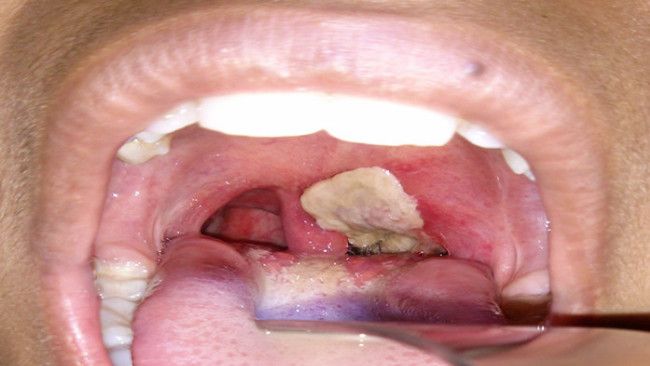

Racun yang dihasilkan bakteri penyebab difteri akan menyebabkan kematian jaringan, termasuk jaringan dalam sistem pernapasan. Akibatnya, jaringan mati tersebut akan membentuk lapisan tebal berwarna abu-abu yang dikenal dengan pseudomembran. Adanya pseudomembran menutupi saluran pernapasan, sehingga menyebabkan kesulitan bernapas.

Tak berhenti di situ, bagian kecil dari pseudomembran dapat terlepas lalu masuk lebih dalam hingga ke paru-paru. Alhasil, timbul reaksi peradangan luas pada paru-paru. Lebih lanjut, muncul risiko hilangnya sebagian atau seluruh fungsi normal paru-paru, di mana kejadian ini dikenal dengan gagal napas.